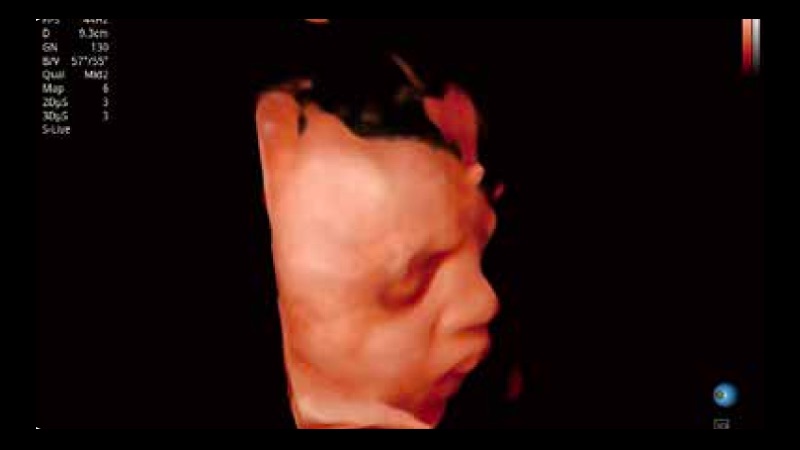

S-Live 高分辨率容积成像

通过仿真成像技术对3D/4D立体数据进行渲染,多种初始光源位置可选,并支持轨迹球360°光源位置自由调节,清晰显示不同方位容积图像细节。

S-Fetus 产科扫查助手

S-Fetus基于大数据深度学习算法,能够帮助您在产前筛查过程中智能识别胎儿标准切面、自动测量并录入报告。一个按键,即可智能、精准、高效地获取胎儿生理指标,极大简化您的产科检查操作。